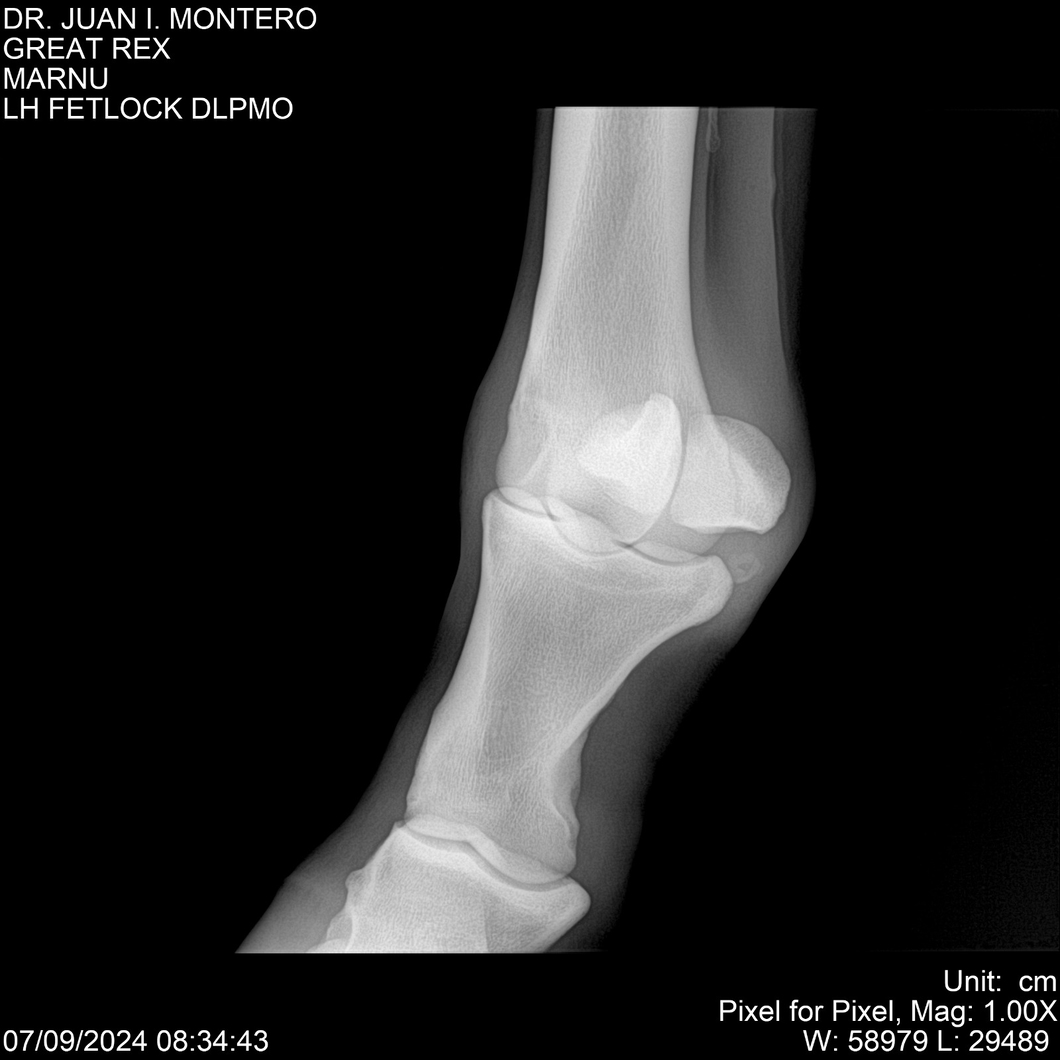

LOTE 4, GREAT REX Lote Anterior Volver al remate Lote Siguiente Ficha Contacto Montevideo - Ficha del Lote Identificador: #282518 Categoría: Yeguarizos Montevideo - 66 Visualizaciones ClicData Contacto Empresa: Abelenda N. R., Walter Hugo Nombre*: Teléfono* : E-mail* : Mensaje Enviar Registrese gratis Este contenido Exclusivo está disponible sólo para usuarios registrados Ingresar